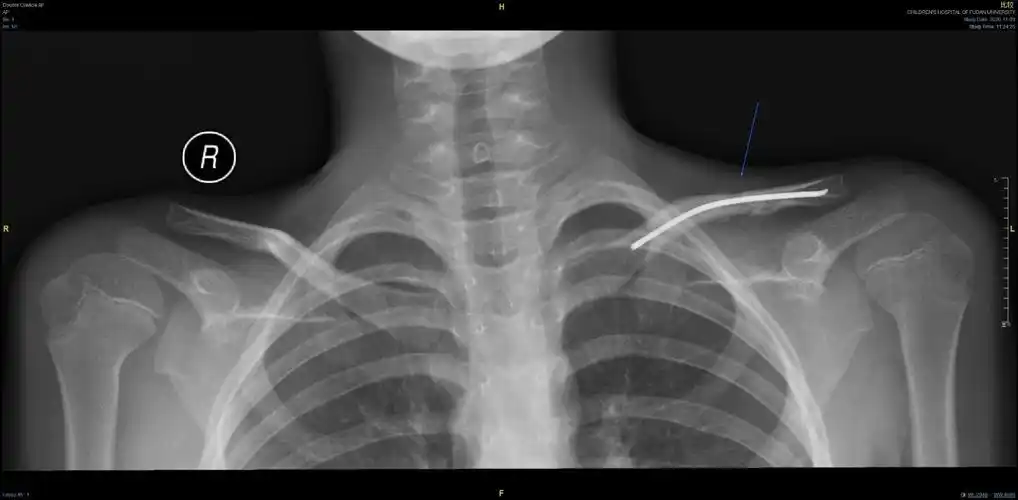

儿童锁骨骨折手术治疗(大于12岁)

右锁骨中段骨折

锁骨x光片

锁骨远端骨折片子如图求给意见欢迎讨论

锁骨骨折

锁骨远端骨折